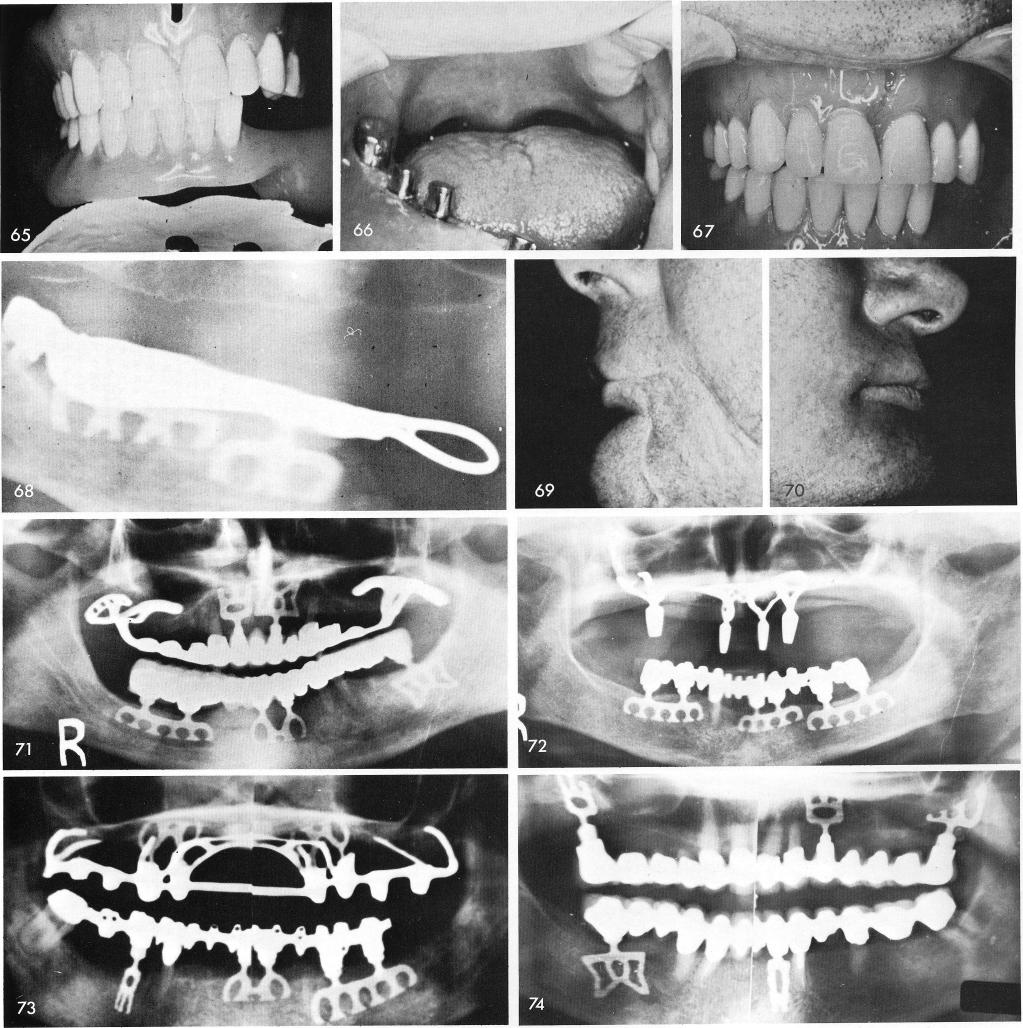

which included a gold coping mesostructure with special built-in attachments for a removable prosthesis with passive type swing-lock attachments, figs. 63, 64. The missing left side of the mandible was filled up with a bulbous type extension off of the left side of the removable pros-thesis, fig. 65. The gold copings were cemented over the implant posts and over the telescopic coping covering the molar tooth, fig. 66, and the prosthesis placed over them, fig. 67. Fig. 68 shows a post-operative x-ray.

The left side of the face with restoration, fig. 69. The right side, fig. 70.

Figs. 71 through 81 show other atypical cases.

1  Gold coping cementation and telescopic coping over mandibular tooth